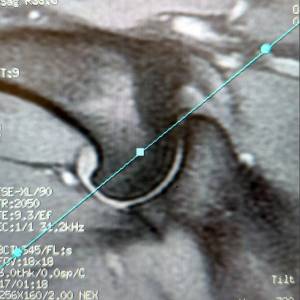

Main Gallery

Playing with a photo gallery function. It is possible to have multiple galleries, each within a namespace.